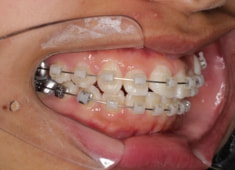

治療開始時

治療開始から5ヶ月後